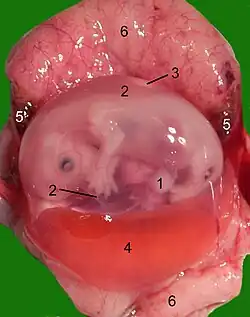

Een foetus in de baarmoeder met de placenta | ||||